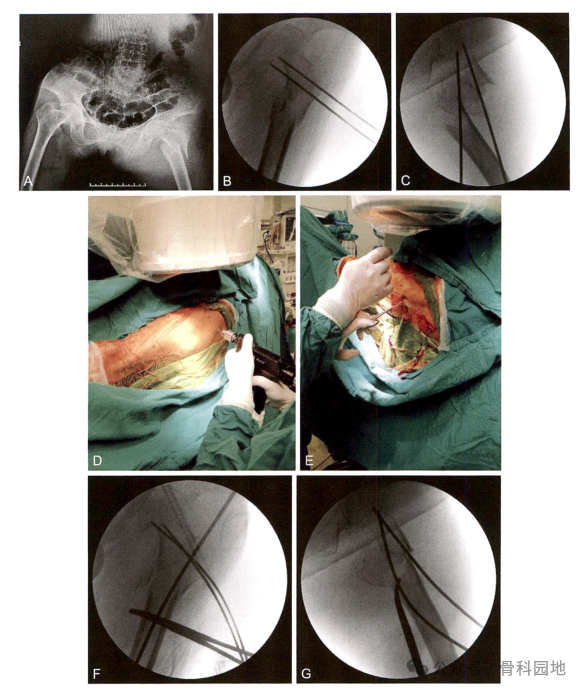

复位技术二(参考实用髓内针治疗学:王秋银主编2023年)

1、

2、

3、

4

5、